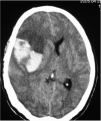

Fig. 1. Tomografía axial computarizada craneal realizada a las 8 horas de administrarse el t-PA en un paciente con un ictus isquémico de arteria cerebral media derecha, donde se observa un voluminoso hematoma parenquimatoso tipo 2 en región frontoparietal derecha.